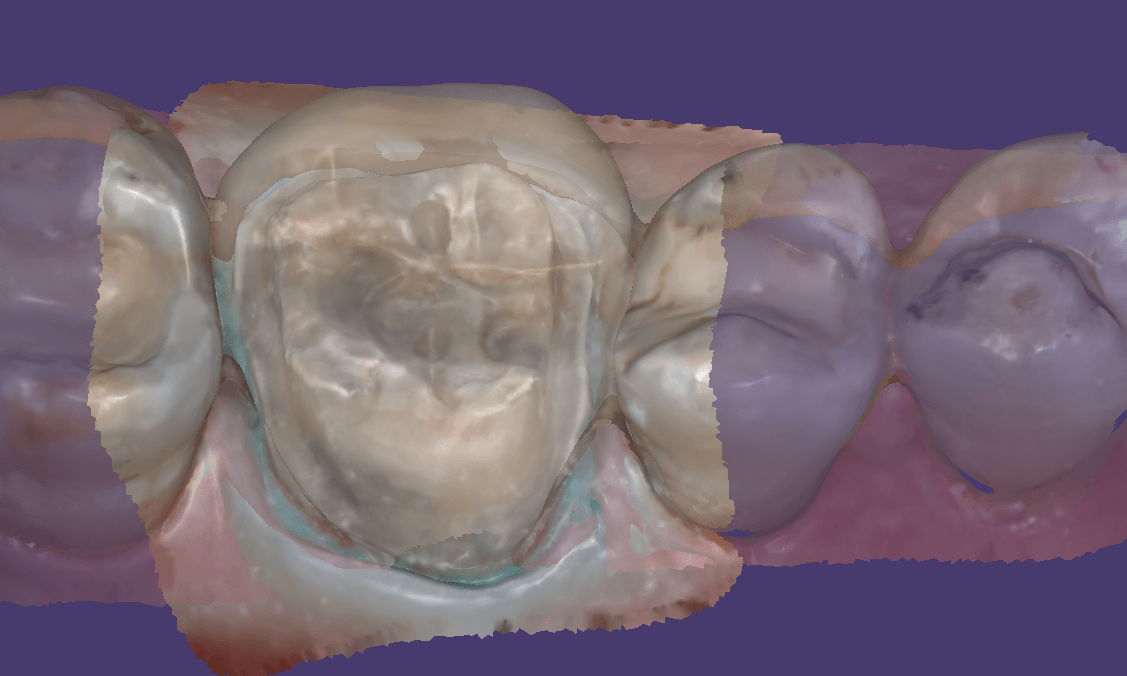

You can then take the prosthesis out of the mouth and continue imaging it and roll over to the intaglio and capture that information.

You can even reline the prosthesis to get the best adaptation possible, scan that, clone the case, and then use the edit tool to crop out everything but the intaglio. What remains is the edentulous ridge that is properly mounted to the opposing arch where you can start designing the desired final restoration.